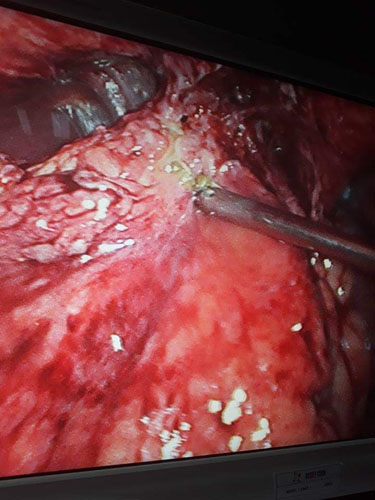

A Young lady who was a small kid...when her mother was operated for a Complex Gastrointestinal condition almost 14 years back by Dr Suddhasattwa Sen suddenly came in with severe blood loss from Gastrointestinal tract with a loss of almost 2 to 3 litres of blood with Shock with fainting . Further stabilisation was done and then extensive investigation revealed not only Piles and GI Ulcers but also SRUS Bleeding ulcers in rectum. A condition called Solitary Rectal Ulcer Syndrome ( a complex and difficult to cure anorectal problem ) . Her hemoglobin dropped to below 7 gm% She finally underwent surgery after 5 days and left home after 2 days post op without any further bleed or problems .